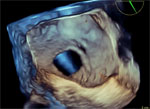

Paciente de sexo femenino, de 52 años de edad, obesa (IMC 54) con antecedentes de comunicación interauricular, sintomática por disnea y palpitaciones. Fue operada hace seis meses, habiéndose efectuado un cierre simple de la comunicación. En el postoperatorio presenta disfunción sinusal, implantándose un marcapaso DDD. Habiendo recomenzado los síntomas en forma similar al preoperatorio, es remitida a nuestro centro para efectuar su evaluación ecocardiogáfica.

Un caso muy interesante, de acuerdo plenamente con los colegas que opinaron de la primera parte, y coincido contigo estimado Víctor, el cierre quirúrgico seguramente fue simple y no con parche, de manera que se abrió el defecto con las consideraciones que hiciste, e incluso me atrevería a decir que el segundo defecto, más pequeño, pudo ser un desgarro a consecuencia del desgarro de suturas del orificio mayor.

La conclusión muestra que la primera indicación debió ser cierre percutáneo, si bien no se pudo incluir el orificio pequeño.

Gracias excelente caso. Coincido con la opinión de que el orificio pequeño pudo ser parte del desgarro al abriese la comunicacón. Interesante no se ve material de sutura.